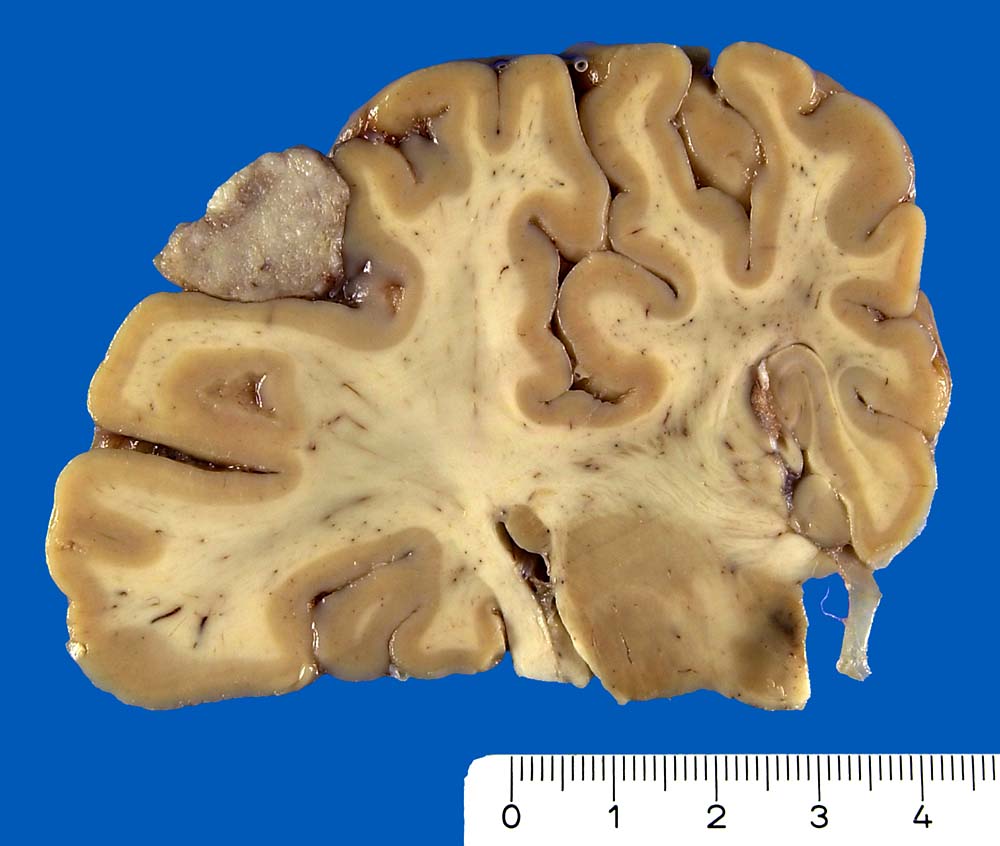

Die meisten Meningeome sind gutartig und fallen in die Kategorie WHO Grad I. Atypische Meningeome (WHO Grad II) machen zwischen 4.7-7.2% aller Fälle aus, anaplastische Menigeome (WHO Grad III) sind noch seltener. Meningeome sind oft multipel bei Patienten mit hereditärer Prädisposition und bei Neurofibromatose 2 sowie bei 10% der sporadischen Fälle. Meist wachsen Meningeome langsam. Sie sind in der Regel scharf begrenzt und sitzen der Dura breitbasig auf. Das Einwachsen von Meningeomgewebe in die Dura mater und/oder die benachbarte Schädelkalotte ist noch kein Malignitätszeichen und noch durchaus vereinbar mit einem benignen Meningeom WHO Grad I. Demgegenüber ist das Einwachsen in das benachbarte Hirnparenchym in aller Regel atypischen oder anaplastischen Meningeomen vorbehalten. Die Konsistenz ist prall-elastisch oder fest und das Tumorgewebe kann fokal verkalkt sein. Das Meningeom en plaque bedeckt flächenhaft die Dura als dünne Platte.

Meningeome können in Abhängigkeit von ihrer Lage vielfältige Symptome verursachen. Lokalisierte oder unspezifische Kopfschmerzen sind häufig. Die Kompression des Hirns kann epileptische Anfälle, fokale Schwäche, Dysphasie, Apathie und Somnolenz auslösen. Meningeome der Schädelbasis können eine Gefässkompression mit konsekutiver Ischämie verursachen. Intraventrikuläre Meningeome können einen obstruktiven Hydrocephalus verursachen. Meningeome in der Nähe der Sella turcica können zu einer Unterfunktion der Hypophyse führen. Typische Symptomenkomplexe sind im Literaturlink tabellarisch dargestellt. Papillenödem, Hirnnervenausfälle, Pyramidenbahnzeichen oder ein Brown Sequard Syndrom durch einseitige Kompression des Rückenmarks stellen mögliche Untersuchungsbefunde dar.

Der Dura breitbasig aufsitzender scharf begrenzter halbkugeliger Tumor.